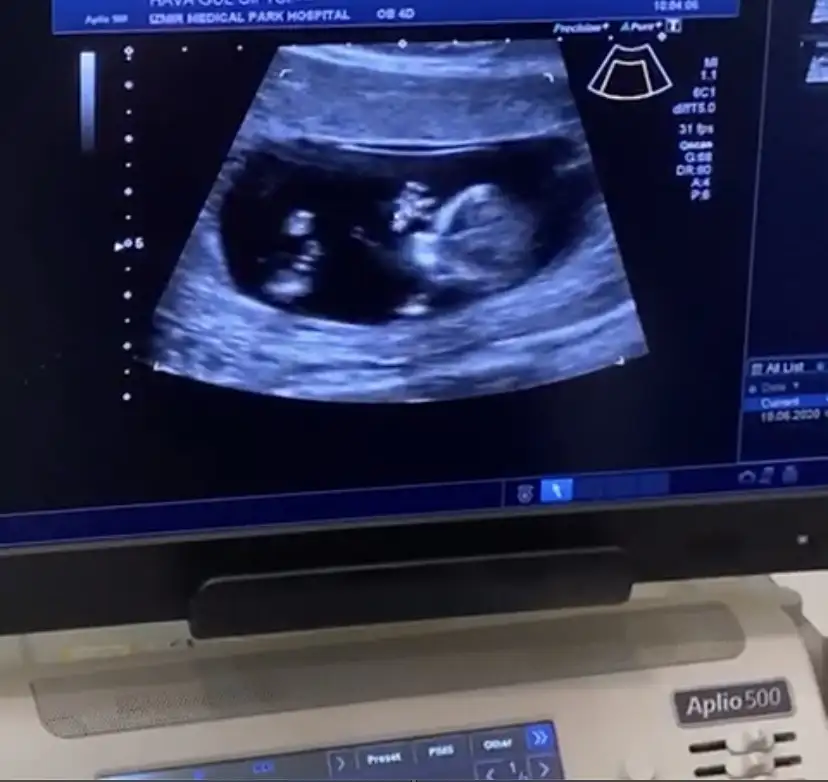

Eklentiler

• 23F5B5B5-951D-4981-84CC-6CD01724D4ED.webp

23F5B5B5-951D-4981-84CC-6CD01724D4ED.webp

28,9 KB · Görüntüleme: 72